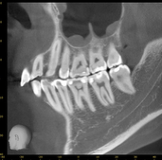

CTで根管形態を三次元的に把握し、他の診査と併せて保存可能性を診断します。

根管の数・弯曲・破折の有無を立体的に確認。

CT画像は3次元的に歯の中の構造を可視化することで、術中も安全に治療をしたり、見逃している根管を明示するのに役立ちます。